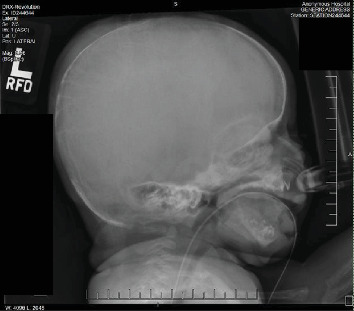

目的:描述一位患有新生儿严重甲状旁腺功能亢进(NSHPT)的女性新生儿的临床表现、诊断挑战和治疗的细节。方法:本病例报告来自回顾性图表回顾。该女婴为近亲父母所生,有多种产前问题,包括妊娠糖尿病、宫内生长受限、羊水过多、产前超声心动图(ECHO)怀疑左心房发育不良。在妊娠37周计划剖腹产后,新生儿表现出中度呼吸窘迫和肋下挛缩。体格检查时,发现颅骨裂、钟形胸部和持续的机械型杂音。结果:出生时的评估显示动脉导管未闭,骨骼结构明显脱矿,肋骨形态不典型。24 h血钙水平升高(14.3 mg/dL),血钙离子升高(2.32 mmol/L), 25-OH维生素D正常(54.2 ng/mL)。一项全面的骨骼调查发现了广泛性骨质减少、干骺端透明和骨折愈合的证据。在43 HOL下重复实验室工作,显示血清钙18.0 mg/dL, iCal 2.67 mmol/L,甲状旁腺激素(PTH)升高2116 pg/mL。NSHPT的诊断基于实验室结果。分子检测证实一个纯合子变异(c.1744T > a;p.Cys582Ser)在钙敏感受体(CaSR)基因中表达,证实了NSHPT的诊断。NSHPT是一种与高死亡率相关的罕见遗传疾病,通常由CaSR基因变异失活引起。患者家族史显示与家族性低钙血症高钙血症(FHH)密切相关,FHH是一种良性疾病,与无症状高钙血症相关,甲状旁腺水平正常至最低限度升高,低钙尿,由CaSR基因杂合失活突变引起。治疗NSHPT通常包括全甲状旁腺或次全甲状旁腺切除术;然而,最初的医疗干预往往是必要的。在此病例中,在成功切除甲状旁腺之前,新生儿接受了降钙素、速尿和静脉输液治疗,以帮助肾脏清除钙。结论:该病例强调了考虑具有复杂临床表现的新生儿罕见遗传疾病的重要性,并肯定了全面咨询和教育的必要性,特别是在近亲父母中,以解决家庭影响并指导适当的干预措施。

Objectives: Describe the details of the clinical presentation, diagnostic challenges, and management of a female neonate with neonatal severe hyperparathyroidism (NSHPT). Methods: This case report was developed from a retrospective chart review. The female infant was born to consanguineous parents-first cousins, with multiple prenatal concerns, including gestational diabetes, intrauterine growth restriction, polyhydramnios, and suspicion of a hypoplastic left atrium on prenatal echocardiogram (ECHO). Following a planned C-section at 37 weeks gestation, the neonate exhibited moderate respiratory distress with subcostal retractions. On physical examination, craniotabes, a bell-shaped chest, and a continuous machinery-type murmur were noted. Results: Evaluation at birth revealed a large Patent Ductus Arteriosus and significant demineralization of skeletal structures with atypical rib morphology. Lab work at 24 h of life (HOL) showed elevated serum calcium level (14.3 mg/dL), ionized calcium-iCal (2.32 mmol/L), and normal 25-OH Vitamin D (54.2 ng/mL). A comprehensive skeletal survey uncovered generalized osteopenia, metaphyseal lucencies, and evidence of healing fractures. Repeat lab work at 43 HOL, showed serum calcium of 18.0 mg/dL, iCal 2.67 mmol/L, and elevated parathyroid hormone (PTH) of 2116 pg/mL. Diagnosis of NSHPT was established based on laboratory findings. Molecular testing confirmed a homozygous variant (c.1744T >A; p.Cys582Ser) in the calcium-sensing receptor (CaSR) gene which confirmed the diagnosis of NSHPT. NSHPT, a rare genetic disorder associated with high mortality rates, is often caused by inactivating CaSR gene variants. The patient's family history revealed a strong correlation with familial hypocalciuric hypercalcemia (FHH), a benign condition associated with asymptomatic hypercalcemia, normal to minimally elevated parathyroid level, and hypocalciuria, it is caused by heterozygous inactivating mutations in the CaSR gene. Treatment of NSHPT typically involves total or subtotal parathyroidectomy; however, initial medical intervention is often necessary. In this case, the neonate underwent medical treatment with calcitonin, furosemide to help facilitate renal clearance of calcium, and intravenous fluids before a successful parathyroidectomy. Conclusions: This case accentuates the importance of considering rare genetic disorders in neonates with complex clinical presentations and affirms the need for comprehensive counseling and education, particularly in consanguineous parents, to address familial implications and guide appropriate interventions.